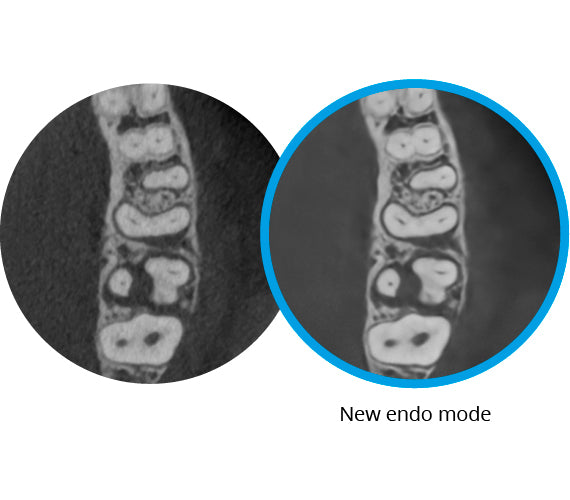

A la vanguardia en la obtención de imágenes de endodoncia

Con frecuencia, el ruido es inherente a la obtención de imágenes de endodoncia debido a la alta resolución necesaria para capturar pequeños detalles. Nuestro modo de imagen de endodoncia 3D basado en IA para las unidades 3D Planmeca Viso combate este problema y permite capturar imágenes CBCT claras y fluidas que son perfectas para la endodoncia. El modo de imagen se encuentra disponible no solo para las entregas de nuevas unidades, sino también para las unidades existentes mediante una actualización de software.